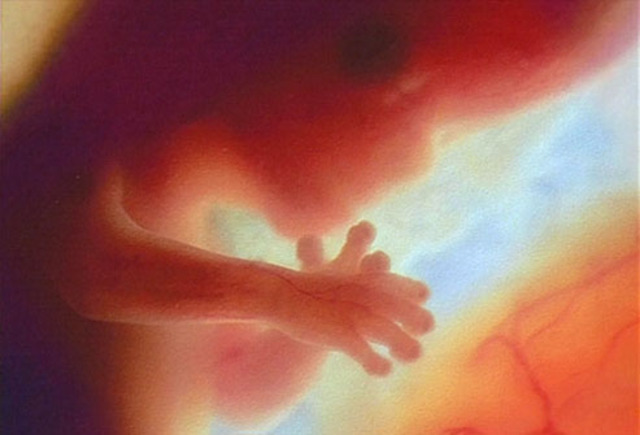

• Month 5 Baby

Month 5 Baby

About 6 1/2 inches (16-18 cm) long, about 4-5 ounces.

Hair, eyelashes, and eyebrows appear.

Teeth continue to develop.

Organs are maturing.

Becomes more active.